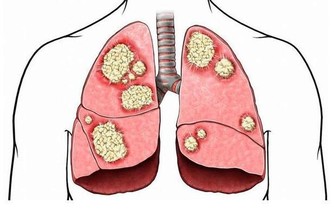

三伏天過去後,夏秋交際的季節,寒溫不調,人體免疫力下降,此時正是肺熱的高發時節,主要是乾咳、痰多、唇部乾燥等現象。

但是,持久劇烈的咳嗽不僅影響休息,還會消耗體力,甚至將病變擴散到鄰近的小支氣管,誘發肺炎、肺氣腫等重大疾病。所以,選止咳藥時,要先弄清病因。

專家提醒,秋季燥熱,傷肝傷脾,表現為咳嗽痰多。

所以,如果咳嗽老不好、經常反复就要注意了,這多半是由以下幾個原因引起,一定要對症治療才有效。